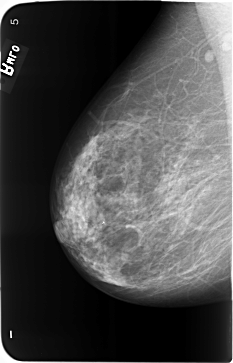

B_3493_1.RIGHT_CC

RIGHT_CC LINES 5808 PIXELS_PER_LINE 3664 BITS_PER_PIXEL 12 RESOLUTION 50 NON_OVERLAY